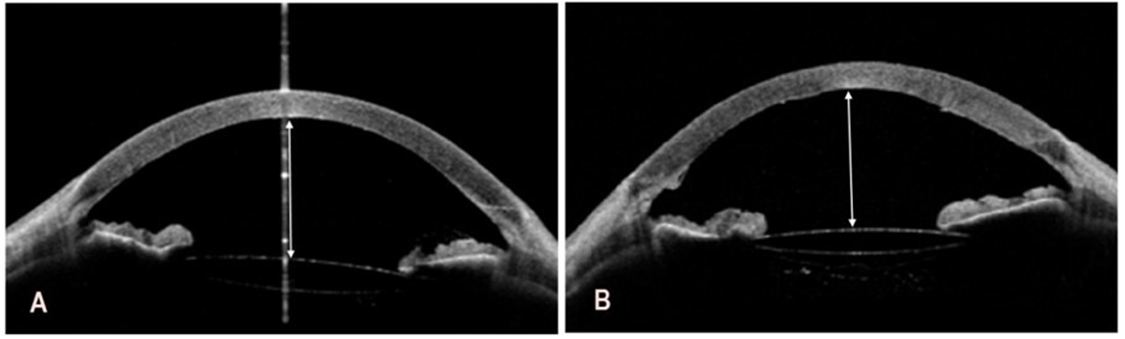

Swept-source OCT using CASIA 2 (Tomey Corporation, Nagoya, Japan) revealed marked shallowing of the anterior chambers, slit-like and nearly completely closed iridocorneal angles, and intumescent lenses in both eyes, particularly in the left eye (Figure 2A,B).

Figure 2: Preoperative swept-source optical coherence tomography of the right and left eye. A. The depth of the anterior chamber to the corneal endothelium in the right eye is 2.03 mm (white double-headed arrow). B. In the left eye, the depth of the anterior chamber to the corneal endothelium is even smaller and amounts to 1.42 mm (white double-headed arrow).

Deepening of the anterior chamber and widening of the iridocorneal angle following the cataract surgeries resulted in a reduced intraocular pressure of 9 mmHg in the right eye and 10 mmHg in the left eye, as measured with iCare tonometry. Anterior segment OCT results are shown in Figure 8A and 8B.

Figure 8: Postoperative swept-source optical coherence tomography of the right and left eye. A. In the right eye, the depth of the anterior chamber to the corneal endothelium is 3.77 mm (white double-headed arrow). B. In the left eye, the depth of the anterior chamber to the

corneal endothelium is 3.78 mm (white double-headed arrow).